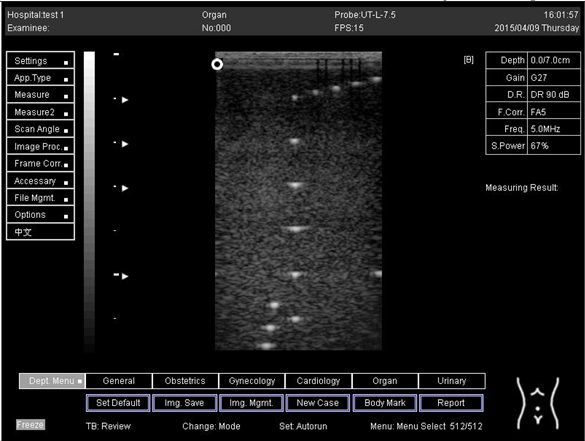

7.0 Biomimetics 07 00130 i035

9.0 Biomimetics 07 00130 i036

The results demonstrate why there is a difference at every depth. As depth increases, the focal zone changes to the lower point of the dots. Hence, penetration increases with depth, and therefore the focal zone changes to the lower point. In this part of the test, the focal zone along the vertical line was found. However, this cannot be done for the 5.0 and 6.0 cm settings of depth by linear probes. This is due to penetration by using depth (Appendix B Table A5, Table A6 and Table A7). In addition, as is known, the focal zone has the best lateral or side-to-side resolution.